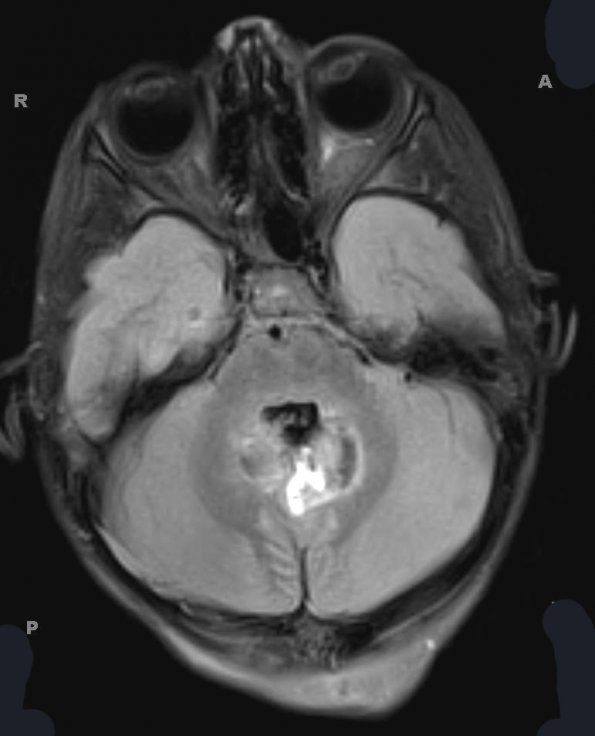

Case 9 History ---- [4yo male with a posterior fossa mass. Operative procedure: Craniotomy for excision of posterior fossa tumor.] ---- 9A1-3 MRI studies: --- 9A1 This FLAIR image shows a hyperintense variegated mass in the cerebellum.